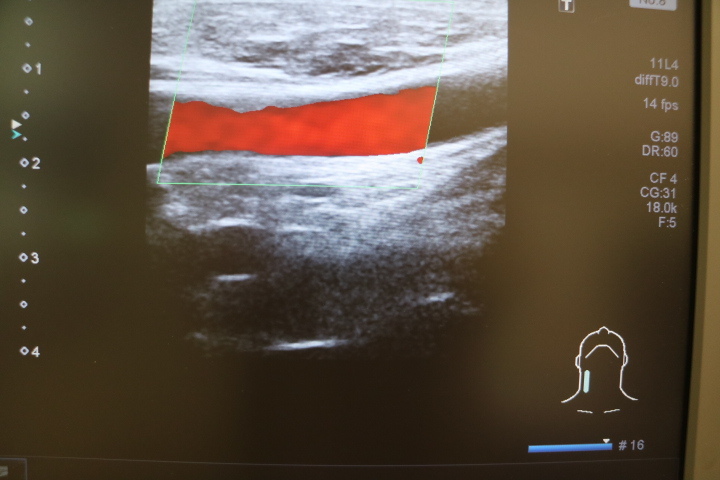

超音波検査(腹部・頸部・四肢など)

・頸部動脈超音波検査(頸動脈の詰まり具合・動脈硬化検査)

・甲状腺・上下肢血管エコー(動脈・静脈血行障害の検査)